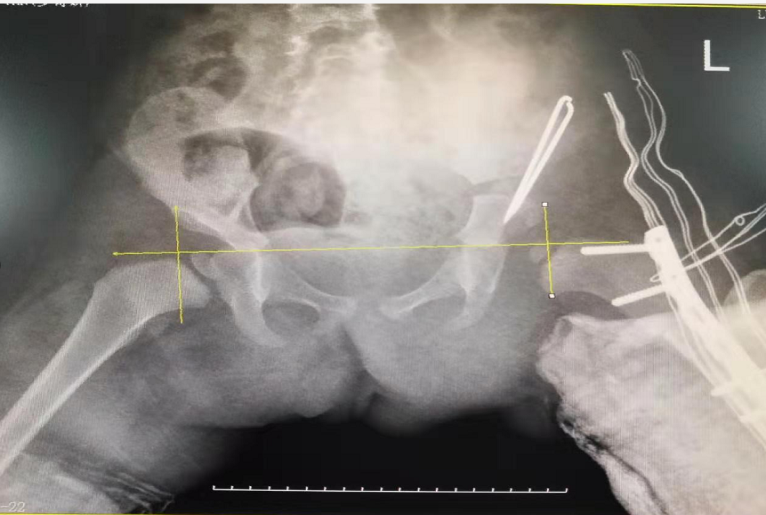

術(shù)前

術(shù)后